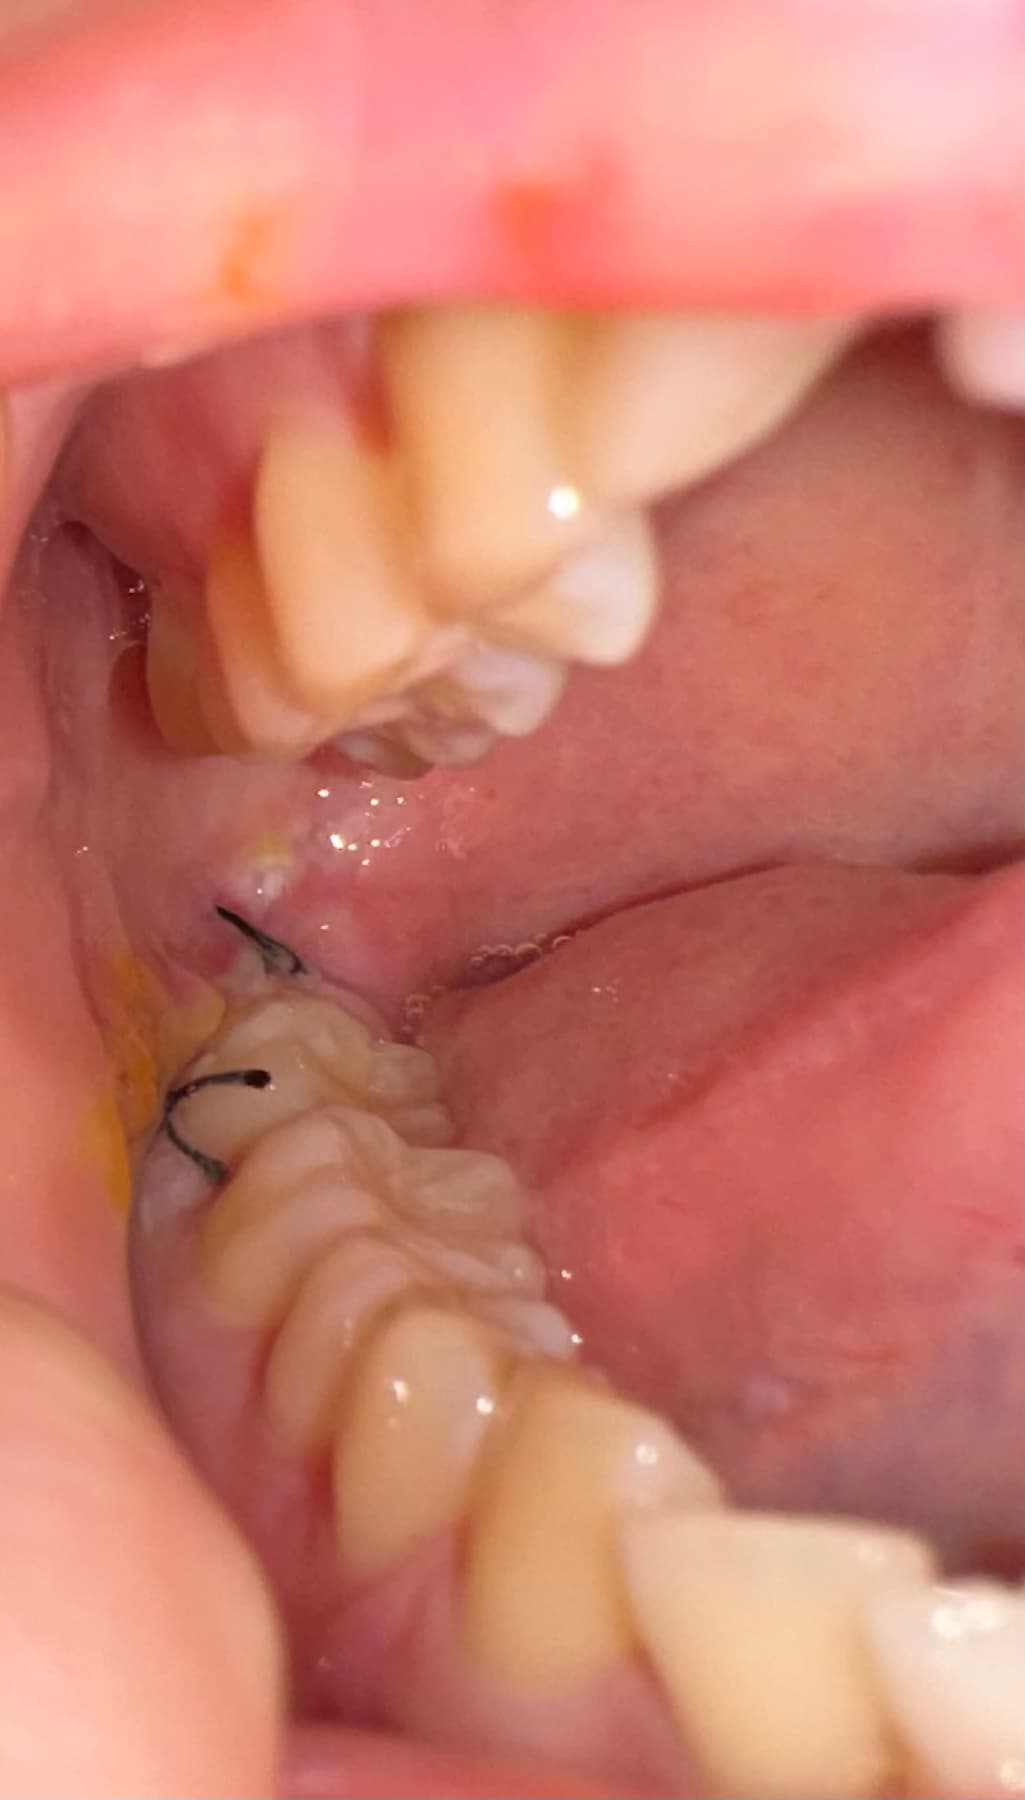

지금 신경쪽 가까운 매복사랑니 뽑은지 6일차인데 아직도 욱신거리고 아파요... 머리가 살짝 울리듯이 아파서 방금 또 약을 먹긴 했는데 아직도 볼쪽이 멍울이 있어서 불편한데.. 왜 저렇게 볼쪽에 노란거랑 흰색이 있는거죠 ?̊̈..염증인건가요 ?̊̈ 아무는중인건가요.. 드라이소켓은아닌가요 ?̊̈.55글자 더 채워주세요.

드라이소켓은 아닌 것으로 보입니다. 살이 씹히거나 한 부분이 조금 있어보이며 크게 문제가 될 것 같진 않습니다.

사진으로 볼때는 크게 이상이 없어 보입니다.

현재 사진상 드라이소켓은 아닌 것으로 보이며, 발치부위 노란색, 흰색부분은 혈전위로 섬유조직이 차오르는 과정입니다. 회복되는 과정으로 정상이나 만약 해당부위가 점점더 통증이 심하거나 고름이 차거나 악취가 발생시에는 치과 진료를 권합니다.